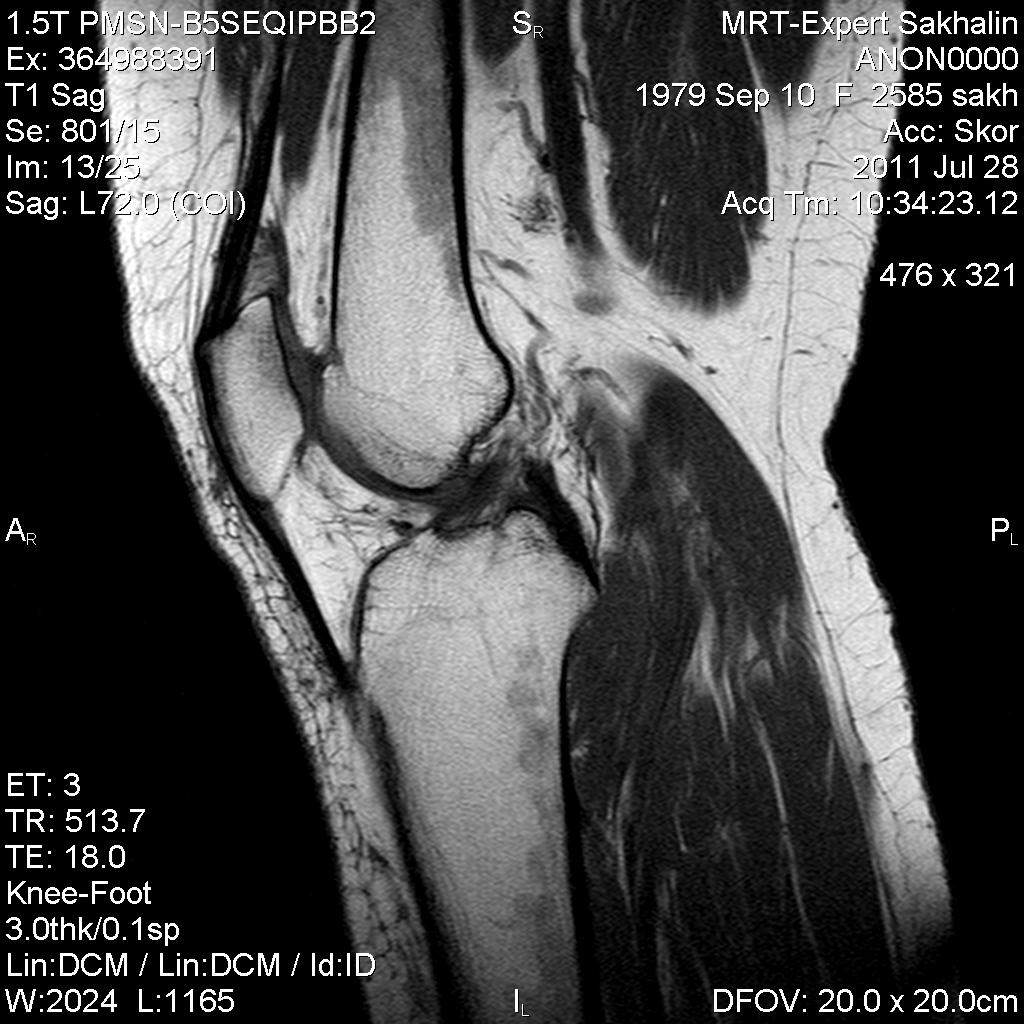

Коленный сустав

Подглядела случай у коллеги.

Что это может быть?

Не вижу криминала. А на что жалуется девушка?

P.S. В костях - это, скорее всего, резидуальный красный костный мозг.

Жалоба у всех одна на всех-болит.

участки гемопоэтического костного мозга